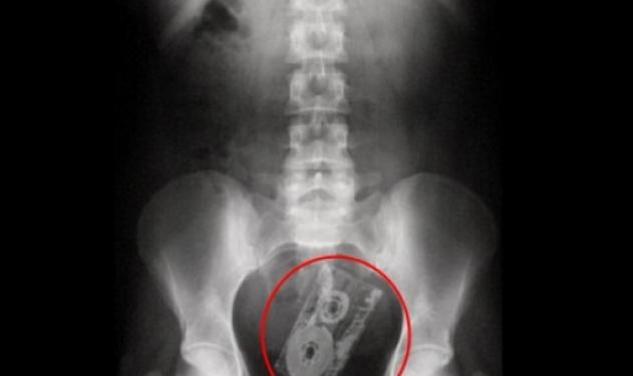

Καρφίτσες, κέρματα, μπαλάκια, δαχτυλίδια, μέχρι και i-pad και κούκλες...barbie έχουν ανακαλύψει μέσα στα σώματα ασθενώ, γιατροί, τόσο στο εξωτερικό όσο και στην Ελλάδα φυσικά.

Σε πολλές περιπτώσεις και αυτό μπορεί να το διηγηθεί ο κάθε γιατρός που έχει αντιμετωπίσει κάποιο παρόμοιο περιστατικό, οι ασθενείς πηγαίνουν με πόνους στην κοιλιά (για παράδειγμα) και όταν ερωτώνται εάν κατάπιαν κάτι κατά λάθος το αρνούνται...